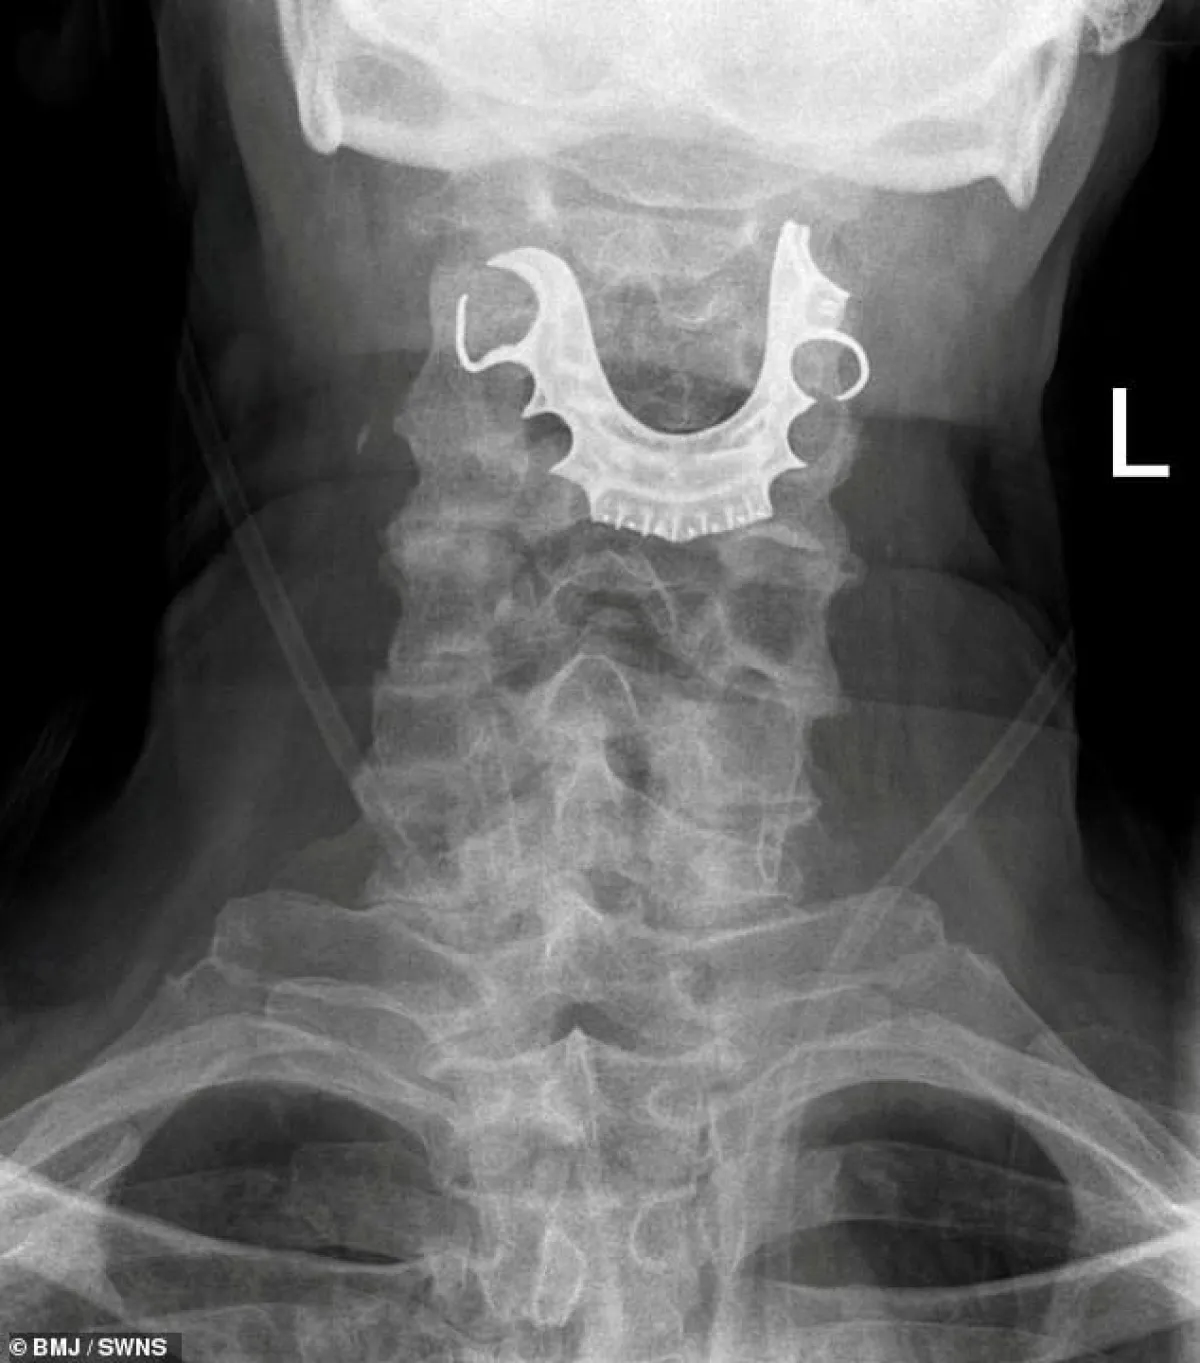

وعندما خضع للفحص، اكتشف الأطباء وجود جسم نصف دائري في حلقه حول الأحبال الصوتية، مما أدى إلى التهابات داخلية، وأثبتت الأشعة الضوئية أن هذا الجسم هو طاقم الأسنان.

وحسب صحيفة "ديلي ميل" البريطانية، و "سكاي نيوز"، فإن الطاقم مكون من شريحة معدنية و3 أسنان أمامية، وقد انحشر في حلق الرجل أثناء جراحة لإزالة ورم حميد من جدار البطن.